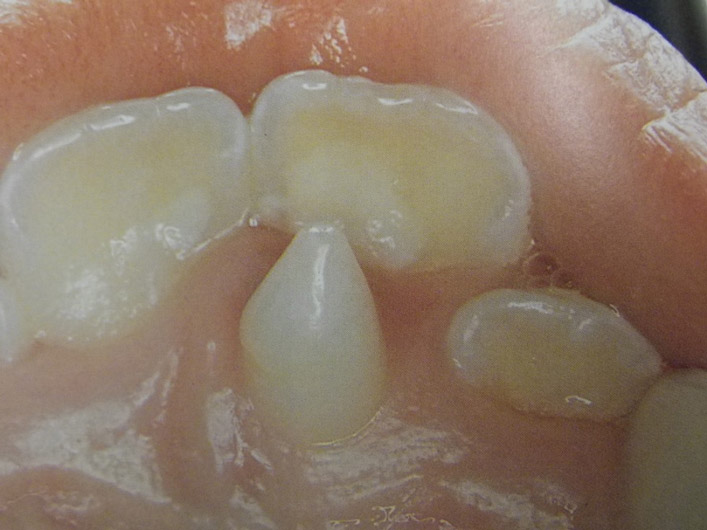

Υπενασβετίωση της αδαμαντίνης

Συνήθως εκδηλώνεται με λευκές, κίτρινες ή καφέ κηλίδες στους τομείς και τους γομφίους, μπορεί όμως να επηρεάσει και άλλα δόντια. Η κλινική εικόνα μπορεί να περιορίζεται μόνο στην εμφάνιση αυτών των κηλίδων, ή να είναι πιο σοβαρή προκαλώντας απώλεια της αδαμαντίνης του δοντιού, με συνέπεια την εμφάνιση ευαισθησίας και πόνου καθώς και τερηδόνας.

Η κατάσταση αυτή της αδαμαντίνης οφείλεται σε διαταραχή της διάπλασής της με αποτέλεσμα την ελλιπή ενσωμάτωση των μετάλλων στη δομή της. Έχουν ενοχοποιηθεί διάφοροι παράγοντες (περιβαλλοντικοί, ασθένειες της μητέρας και του βρέφους, διατροφή κ.ά.) οι οποίοι μπορούν να προκαλέσουν αυτές τις διαταραχές.

Σημαντική είναι η έγκαιρη διάγνωση από τον παιδοδοντίατρο και η εφαρμογή ενός ολοκληρωμένου προληπτικού προγράμματος προστασίας αυτών των δοντιών προκειμένου να διατηρηθούν υγιή.